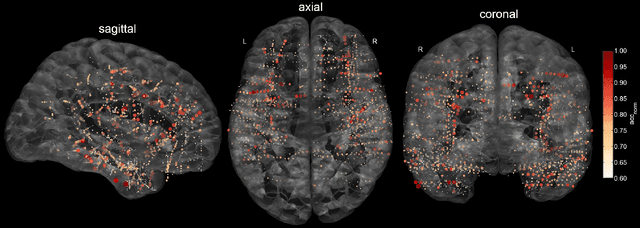

Abstract:Deep learning techniques have revolutionized the field of machine learning and were recently successfully applied to various classification problems in noninvasive electroencephalography (EEG). However, these methods were so far only rarely evaluated for use in intracranial EEG. We employed convolutional neural networks (CNNs) to classify and characterize the error-related brain response as measured in 24 intracranial EEG recordings. Decoding accuracies of CNNs were significantly higher than those of a regularized linear discriminant analysis. Using time-resolved deep decoding, it was possible to classify errors in various regions in the human brain, and further to decode errors over 200 ms before the actual erroneous button press, e.g., in the precentral gyrus. Moreover, deeper networks performed better than shallower networks in distinguishing correct from error trials in all-channel decoding. In single recordings, up to 100 % decoding accuracy was achieved. Visualization of the networks' learned features indicated that multivariate decoding on an ensemble of channels yields related, albeit non-redundant information compared to single-channel decoding. In summary, here we show the usefulness of deep learning for both intracranial error decoding and mapping of the spatio-temporal structure of the human error processing network.